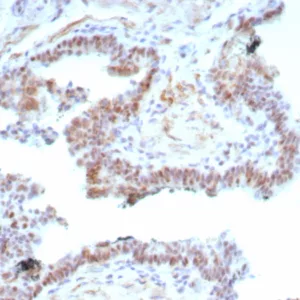

Formalin-fixed, paraffin-embedded human prostate carcinoma stained with Androgen Receptor Recombinant Mouse Monoclonal Antibody (rDHTR/6818). Inset: PBS instead of primary, secondary antibody control.

Androgen Receptor is a member of the superfamily of ligand responsive transcription regulators. The androgen receptor functions in the nucleus where it is believed to act as a transcriptional regulator mediating the action of male sex hormones. The androgen receptor has wide distribution and can be demonstrated by immunohistochemistry in several tissues including prostate, skin, and oral mucosa. Androgen receptor has been reported in a diverse range of human tumors including osteosarcoma, and in prostatic carcinoma androgen receptor expression may be of clinical relevance.